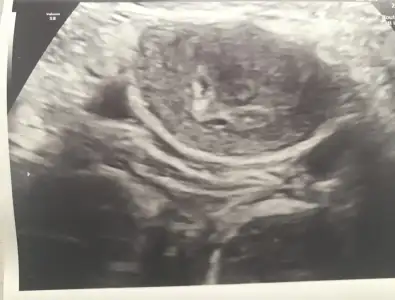

Arkadaşlar benim çatlatma iğnesinden sonra 12. Gün beta 82 çıkmıştı ve iki günde bir ise iki katı artmıştı iğnenin 21. Günü keseyi gördük karından ultrason ile beta ise 3000 lerdeydi. Resimde üstteki keseymiş alttaki kan akıntısı da olabilir bi kese daha da olabilir dedi. Haftaya kalp atışı duymaya gittiğimizde daha net söyleyecekmiş. İkiz bebek anneleri bi fikriniz var mı

• 995101AF-1F87-424D-9387-4D570DE0929C.webp